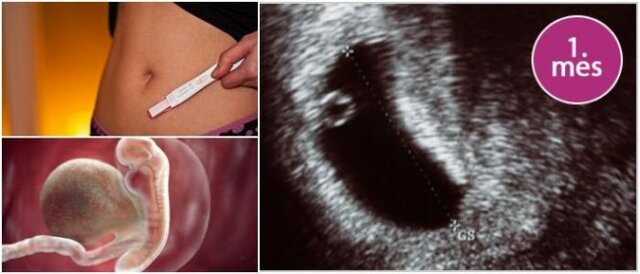

• PRIMER MES

PRIMER MES

En los primeros días el embrión mide 1 mm. Comienzan a

formarse el sistema nervioso y el corazón, que late cerca de la tercera semana.